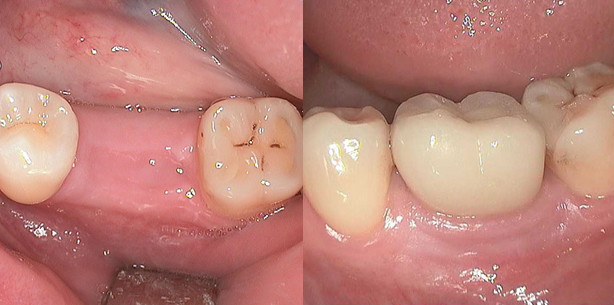

Nach erfolgter Farbbestimmung wurde dann eine einzeitige einphasige Abformung mit Impregum vorgenommen (Abb. 7). Im Anschluss stellten wir eine provisorische Krone aus Kunststoff her (Abb. 8 und Abb. 9). 11 Tage nach der Implantation haben wir die provisorische Krone entfernt und die definitive Zirkondioxidkrone mit Harvardzement eingegliedert (Abb. 10, Abb. 11 und Abb. 12).

Die Abschlussbilder 13 –16 zeigen die klinische Situation nach 2 Jahren. Sehr gut zu sehen ist bei dem Vergleich der Bilder 11 und 15/16 der Zuwachs an Gingiva. Dieses als Gingiva-Attachment-Effekt (GAE) bezeichnete Zahnfleischverhalten resultiert aus der ca. 1 mm breiten, dicht aufliegenden Keramik und bildet sich sehr oft, bei den von uns genutzten Techniken, nach mehreren Monaten aus.